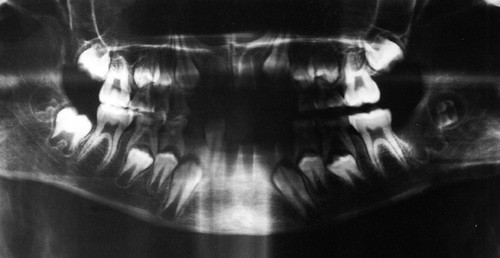

Forfatteren har tidligere foretatt undersøkelser, også med røntgenteknikk, av kraniemateriale fra middelalderens Oslo (3). Av dette er det tidligere undersøkt fire kranier fra Nonneseter kloster. Et av disse er omtalt i en tidligere artikkel (4). To av de undersøkte har vært barn som har vært begravet på Nonneseter klosters kirkegård. Det foreligger ikke annet skjelettmateriale som kan identifisere dem. Kjønnsbestemmelse kan ikke foretas med pålitelighet hos barn i lav alder. Aldersbestemmelse kan imidlertid utføres med stor sikkerhet ut fra odontologisk undersøkelse, ved direkte inspeksjon og med støtte i røntgenundersøkelse. Det foreligger hos begge blandingstannsett, og alderen kan med stor sikkerhet fastsettes til 8 – 9 år (fig 1, fig 2).